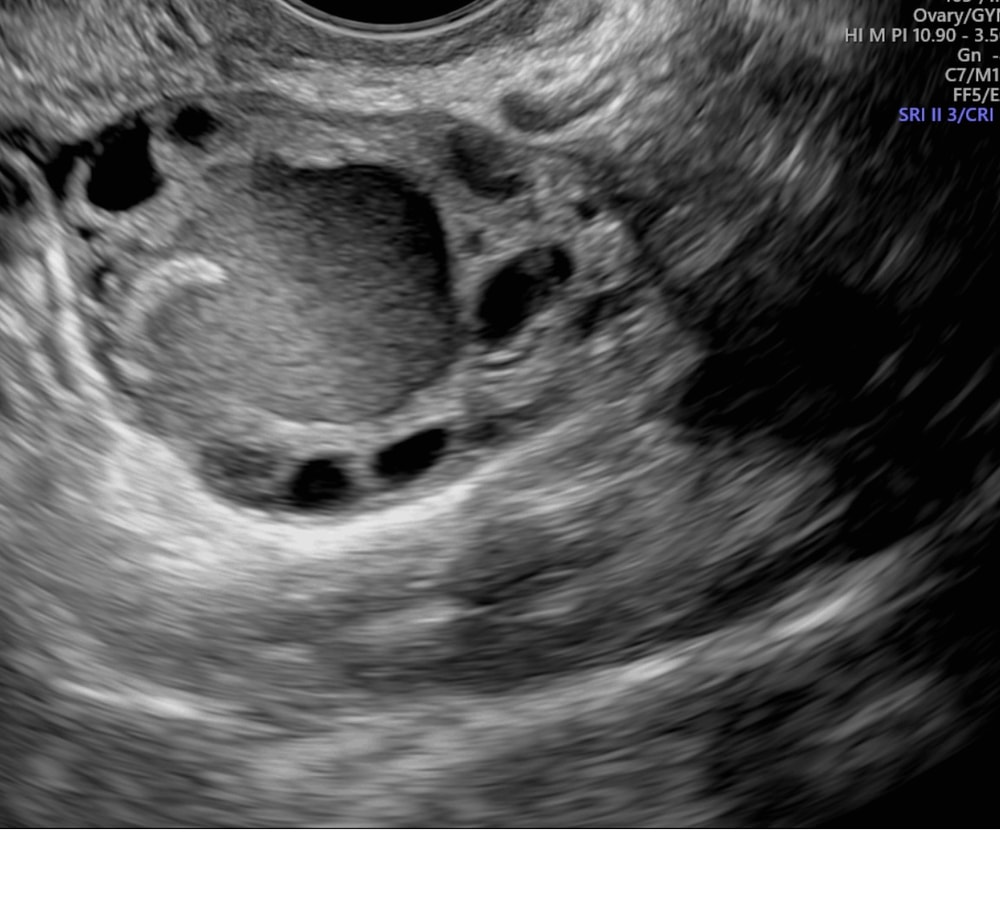

Прикладываю результаты узи, за столько лет обнаружили только сейчас, планируем беременность. Все здоровы , кроме этих кист. Врач скорей всего отправит на МРТ. Прошу дать совет, если врач скажет удалять ?То лучше удалить до беременности? Как это все пережить?! очень страшно!кто удалял повлияло ли на зачатие?

"На УЗИ-снимке врач описывает два жидкостных образования: 7 мм и 25 мм. Образования с мелкодисперсной взвесью - это как раз эндометриоидные кисты. Тот гиперэхогенный компонент, который Вы выделили на снимке, это пристеночное гиперэхогенное аваскулярное образование в составе эндометриоидной кисты. Такие образования бывают очень часто, это не дермоидная киста.